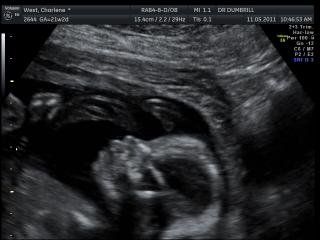

Home Birth and Hospital Birth Gallery hdrhdrbtyhdrbmdbty bdrbty Processed with VSCO with fn16 presetbty dav